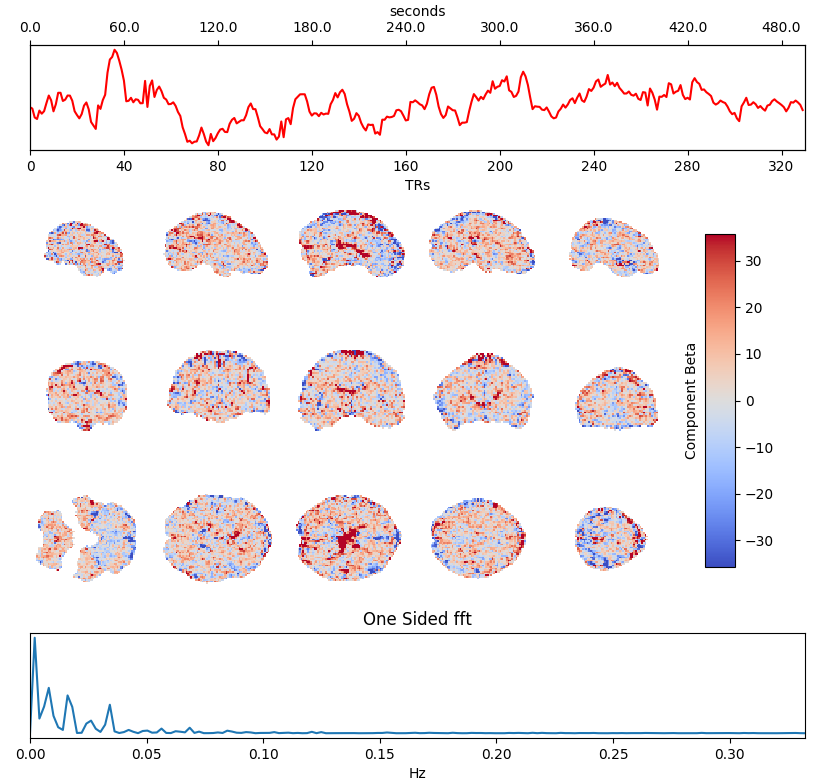

ICA denoising

Independent Component Analysis (ICA) is commonly used to remove motion effects and other sources of noise from fMRI data

Motion

Motion + MB artefact

CSF pulsations

Griffanti et al. 2014 (NeuroImage), 2017 (NeuroImage), The tedana Community et al. 2021 (Zenodo)

Which ICA denoising?

What is the best way to denoise BH data after ICA?

being too aggressive might remove the signal of interest,

but being too conservative might keep too much noise in the model.

Methods: ME-ICA based denoise

What is the best way to denoise BH data after ICA?

being too aggressive might remove the signal of interest,

but being too conservative might keep too much noise in the model.

- Aggressive model: nuisance regression using only noise ICA-components (ME-AGG): $$ Y_{OC} = P_{ET}CO_2{hrf} + Mot + Poly + [IC_{rej} \perp (Mot,Poly) ] + n $$

- Moderate model: noise components are orthogonalised w.r.t. the CO2 trace (ME-MOD): $$ Y_{OC} = P_{ET}CO_2{hrf} + Mot + Poly + [IC_{rej} \perp (P_{ET}CO_2{hrf},Mot,Poly) ] + n $$

- Conservative model: noise components are orthogonalised w.r.t. the CO2 trace and the other components (ME-CON): $$ Y_{OC} = P_{ET}CO_2{hrf} + Mot + Poly + [IC_{rej} \perp (P_{ET}CO_2{hrf},IC_{acc},Mot,Poly) ] + n $$

- Optimal combination only (OC-MPR): $$ Y_{OC} = P_{ET}CO_2{hrf} + Mot + Poly + n $$

- Single echo only (second echo used as proxy, SE-MPR): $$ Y_{SE} = P_{ET}CO_2{hrf} + Mot + Poly + n $$

We set up a simultaneous estimation and denoise step, considering motion parameters,

their derivative, Legendre polynomials to the fourth order, and:

- Aggressive model: nuisance regression using only noise ICA-components (ME-AGG): $$ Y_{OC} = P_{ET}CO_2{hrf} + Mot + Poly + [IC_{rej} \perp (Mot,Poly) ] + n $$

- Moderate model: noise components are orthogonalised w.r.t. the CO2 trace (ME-MOD): $$ Y_{OC} = P_{ET}CO_2{hrf} + Mot + Poly + [IC_{rej} \perp (P_{ET}CO_2{hrf},Mot,Poly) ] + n $$

- Conservative model: noise components are orthogonalised w.r.t. the CO2 trace and the other components (ME-CON): $$ Y_{OC} = P_{ET}CO_2{hrf} + Mot + Poly + [IC_{rej} \perp (P_{ET}CO_2{hrf},IC_{acc},Mot,Poly) ] + n $$

- Optimal combination only (OC-MPR): $$ Y_{OC} = P_{ET}CO_2{hrf} + Mot + Poly + n $$

- Single echo only (second echo used as proxy, SE-MPR): $$ Y_{SE} = P_{ET}CO_2{hrf} + Mot + Poly + n $$

Alternative ICA based denoise (sequential)

What is the best way to denoise the data after ICA?

Regression based:

Aggressive approach: nuisance regression using only the rejected components.

Non aggressive (partial regression) approach: all the components are considered, but only the rejected components are regressed out of the data.

Orthogonalised approach: the rejected components are orthogonalised with respect to the other components.

4D-based approach (similar to M/EEG): reconstruct volumes on noise, then subtract it from the original data.